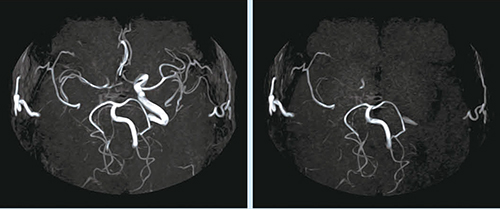

同院では,脳血管領域でBeamSatを用いた3D TOF(Time of Flight)MRAによる頭部血管の血行動態の評価を行っている。BeamSatは,円筒状のRFパルス(BeamSatパルス)によって特定の血管の信号を抑制することで,血行動態の情報を付加する撮像法である。黒瀬TSはBeamSatについて,「例えば右の内頸動脈に狭窄があり血流が低下しているにもかかわらず,右の中大脳動脈などの描出がある場合に,左内頸動脈にBeamSatパルスを印加することで血流情報を抑制し,脳血管の描出の変化を見ることで,血行動態や養生血管の特定を行うことができます」と説明する。

■症例1:BeamSat

右ICAsiphonの広範な狭窄〜閉塞による右MCAの信号低下。臨床所見では外来内服治療中,左半身麻痺を生じ,TIAを繰り返していた。DWIにて高信号を認め,STA-MCAバイパス施行となった。

3D-TOF MRA,TR:37.8,TE:6.9,FA:30°,3スラブ